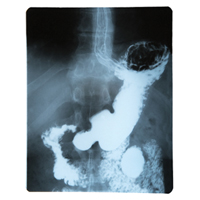

Эволюционные процессы, приводящие к появлению аппендикса, его связь со слепой кишкой и другими участками желудочно-кишечного тракта остаются неизвестными. В ходе данной работы ученые проанализировали пищеварительную систему, пищевые привычки, экологические и социальные особенности у 533 видов млекопитающих, обращая внимание на наличие или отсутствие аппендикса. Используя филогенетический анализ, они отметили, что появившись у одного из видов, червеобразный отросток сохранился и у других. Это, согласно теории эволюции, свидетельствует о том, что его присутствие целесообразно и он выполняет какую-то функцию. Исследователи обратили внимание, что у животных, у которых присутствовал аппендикс, отмечалась высокая плотность лимфоидной ткани на участке, соединяющем толстый и тонкий кишечник. Эта ткань связана с иммунной системой и ростом нормальной микрофлоры кишечника. Данная закономерность, по всей видимости, свидетельствует об истинной роли аппендикса в организме, заключающейся в адаптивной иммунной функции.

Ученые предположили, что на самом деле аппендикс может служить резервуаром для бактерий, составляющих кишечную микрофлору. Так они сохраняются даже во время инфекционных патологий, сопровождающихся диареей. Именно эти бактерии, как известно, стимулируют иммунную систему, синтезируют гормоны и незаменимые витамины, а также участвуют в переваривании пищи. Следовательно, люди без аппендикса дольше восстанавливаются после перенесенных кишечных инфекций.